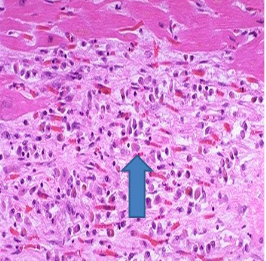

When would this histopatholigcal slide from an MI likely to have occurred

Less than 1 day

Less than 7 days accute inflam

1-3 week

3-6 weeks